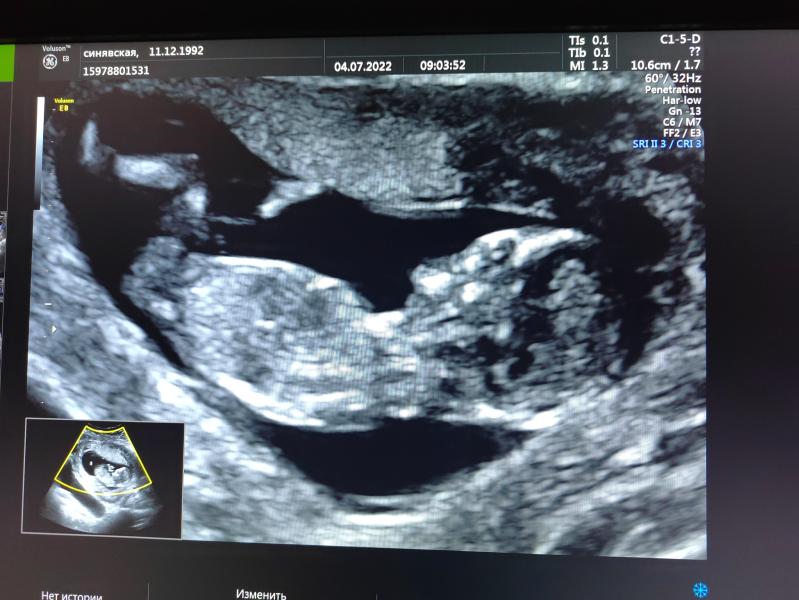

Первый скрининг 04.07.2022: все хорошо! Как я волновалась без мужа у кабинета врача

04.07.2022 был наш первый скрининг😁 Радует, что всё хорошо🙏❤️ Без мужа наверное я бы с ума сошла от волнения перед дверью кабинета🤪